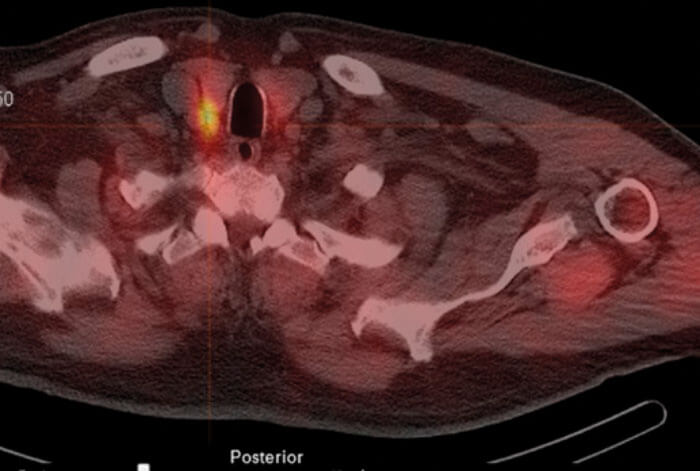

As with all parathyroid surgery, ultrasound of neck is used to check thyroid gland integrity. Our preference for location of the parathyroid adenoma is using single-photon emission computed tomography (Spect CT) and nuclear medicine (NM) scans (see Figure 1).

Figure 1. Spect CT scan in axial plane showing position of the parathyroid adenoma highlighted.